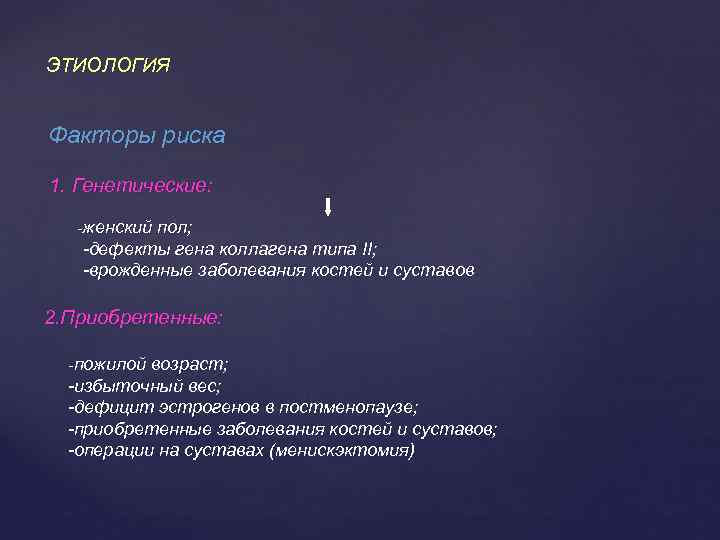

ЭТИОЛОГИЯ Факторы риска 1. Генетические: -женский пол; -дефекты гена коллагена типа II; -врожденные заболевания костей и суставов 2. Приобретенные: -пожилой возраст; -избыточный вес; -дефицит эстрогенов в постменопаузе; -приобретенные заболевания костей и суставов; -операции на суставах (менискэктомия)

ЭТИОЛОГИЯ Факторы риска 1. Генетические: -женский пол; -дефекты гена коллагена типа II; -врожденные заболевания костей и суставов 2. Приобретенные: -пожилой возраст; -избыточный вес; -дефицит эстрогенов в постменопаузе; -приобретенные заболевания костей и суставов; -операции на суставах (менискэктомия)